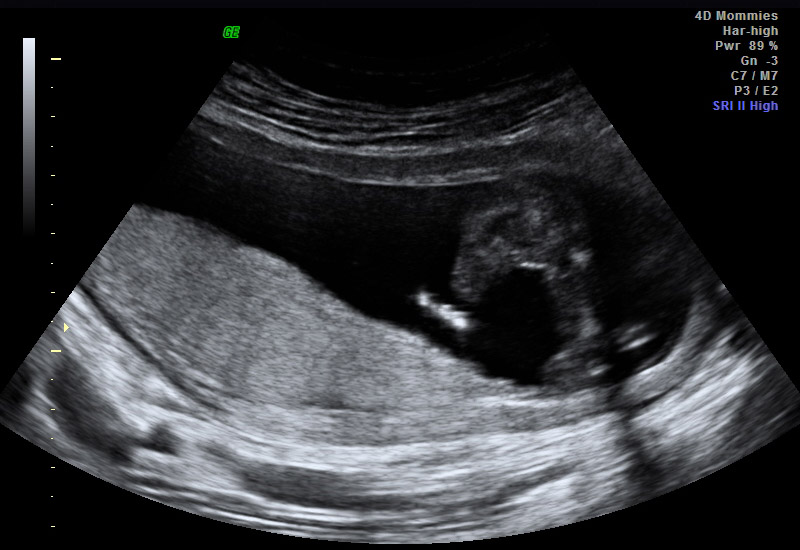

Had an elective u/s today @ 15 wks. Tech said girl, looking for some confirmation. The third pic has me a little confused, but she said that wasn't a good shot. Looking for you wonderful ladies to weigh in! TIA!! Attachment 23883Attachment 23884Attachment 23885